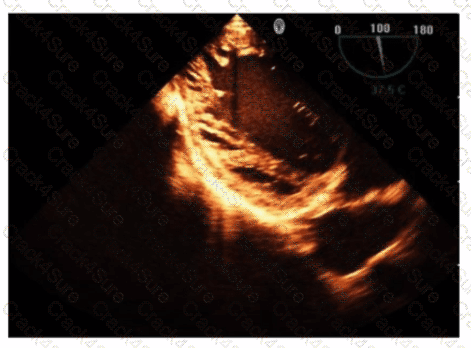

Which technique best determines a trileaflet aortic valve from a bicuspid aortic valve?

Which view is best for assessing atrial situs in the presence of congenital heart disease?